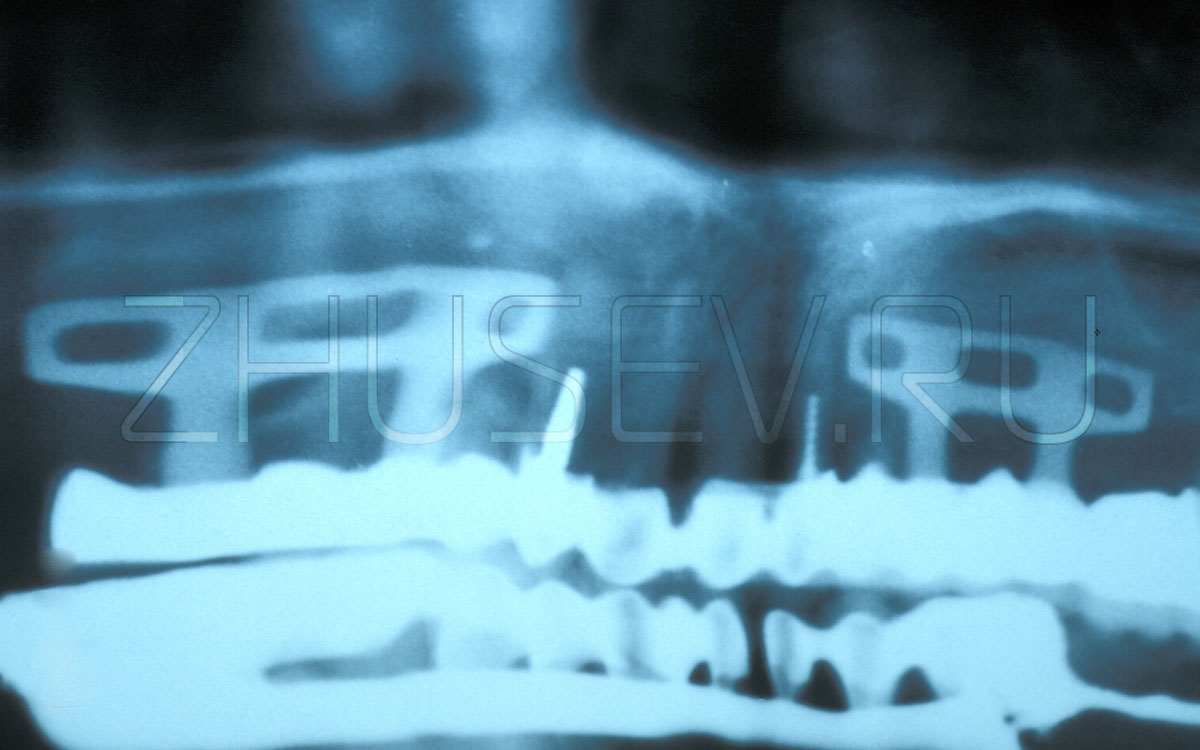

Редкий экземпляр эндосто-субпериостального имплантата.

Очень часто слесарное-строительные технологии прямиком переносили в операционную. Правда, очень быстро стало ясно, что кость это не стена в квартире и не входная дверь!